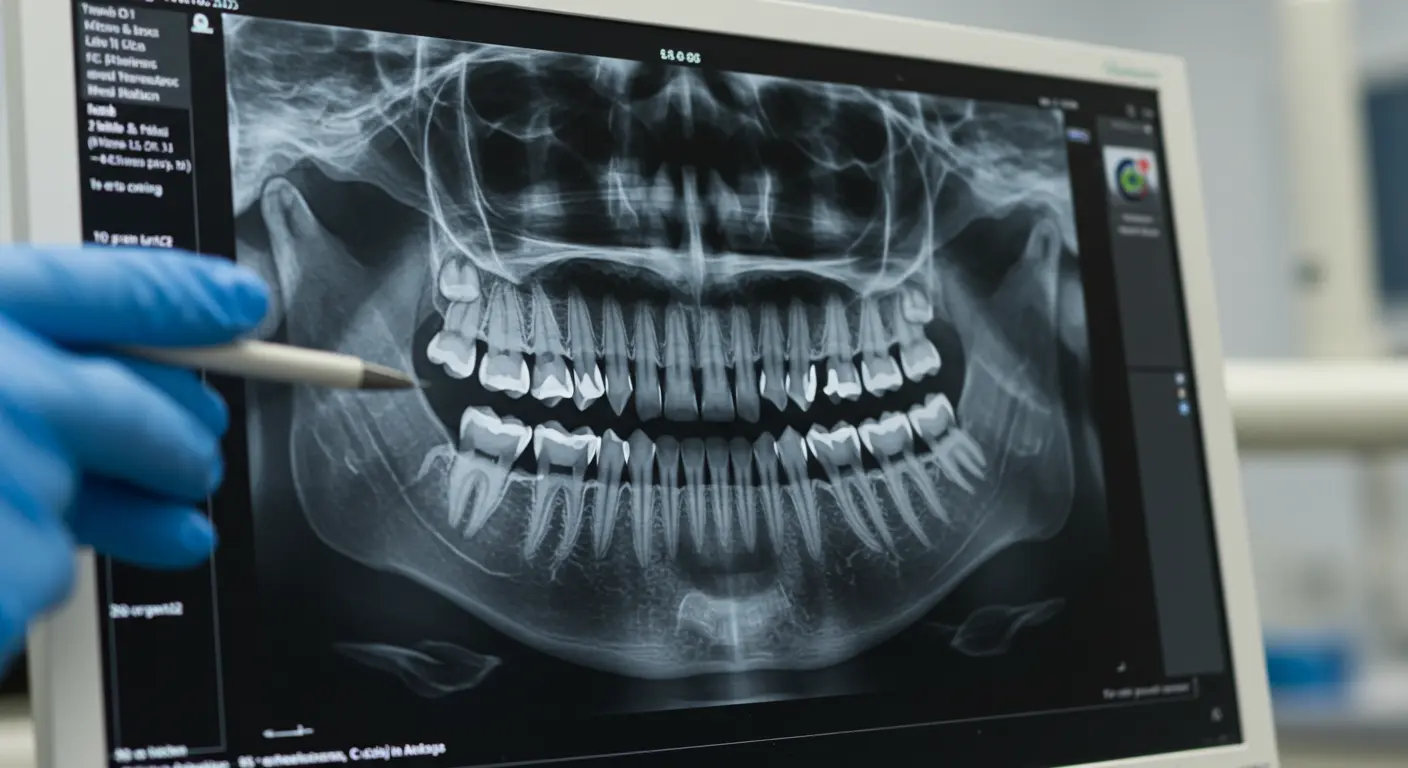

3. Dental X-Rays

Purpose: Evaluate internal structures.

Detects cavities, root canal issues, or bone loss.

Checks tooth root positioning and bone density.

Ensures implants or restorations have adequate support.

Types of X-rays:

Periapical X-rays: Focus on individual teeth and surrounding bone.

Panoramic X-rays: Provide a full view of the upper and lower jaws.